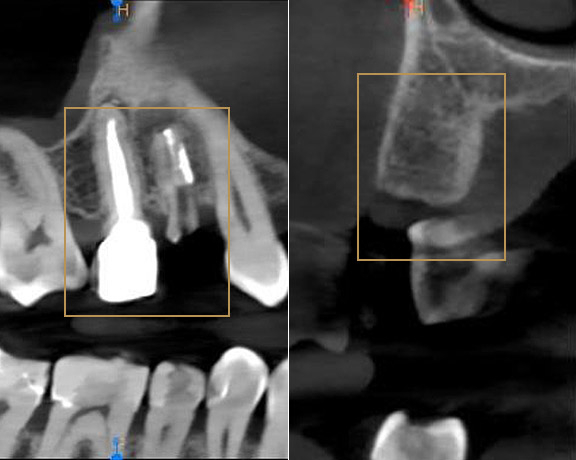

Ekstrakcja zęba przy wsparciu osocza bogatopłytkowego (frakcja L-PRF). Kontrola.

Nasz wieloletni Pacjent zgłosił się do gabinetu ze złamanym zębem (14). Wnikliwe badanie diagnostyczne wykazało, że nie tylko korona została odłamana, ale doszło również do pęknięcia korzenia. Niestety w takim przypadku wskazaniem jest usunięcie zęba.

Zabieg ekstrakcji wsparliśmy wypełnieniem zębodołu osoczem bogatopłytkowym. Wykorzystanie osocza (wyodrębnionej specjalnej frakcji L-PRF z krwi własnej pacjenta) wspiera poprawne gojenie rany oraz przyśpiesza regenerację tkanek. Osocze stanowi naturalny opatrunek, pozwala również na uniknięcie tzw. suchego zębodołu.

Pacjent zgłosił się po roku, zgodnie z planem uzupełnienia brakującego zęba. W badaniu radiologicznym widzimy dobrze wygojony wyrostek zębodołowy, gotowy do przyjęcia implantu. Wykorzystanie osocza podczas ekstrakcji z pewnością przyczyniło się do dobrego przygotowania miejsca pod implantację.